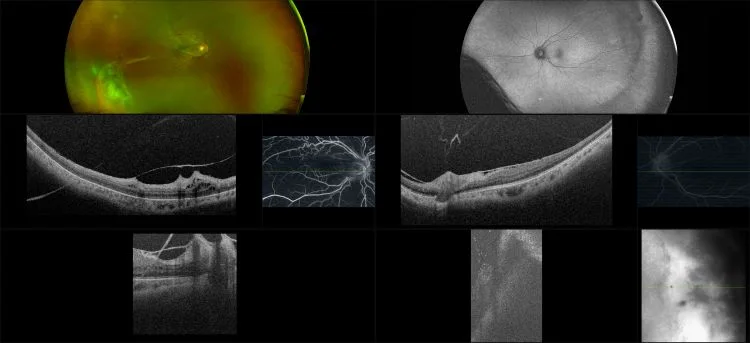

Sickle Cell Retinopathy

Sickle cell retinopathy when sickled red blood cells block small vessels in the eye, new blood vessels form that are weaker and can cause bleeding into the eye.